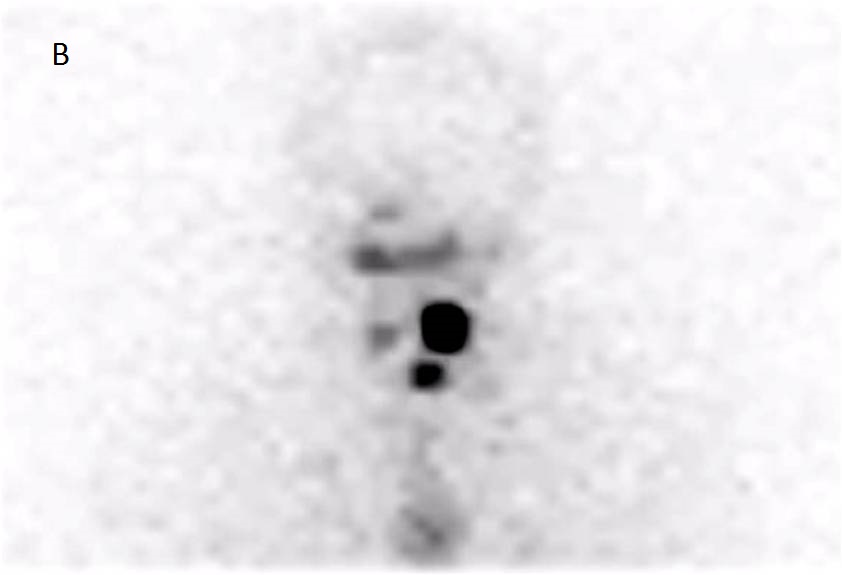

Anterior neck (A) and thoracic (B) views show 3 foci of I-131 uptake probably due to remnant tissue in the thyroid bed (black arrow). Note, Mid Thoracic irregulas uptake, less intense. Spect-CT fusion imagesĀ in (C) and (D) slices, depict anterior localization of the tracer, corresponding to Thymus (yellow arrow).